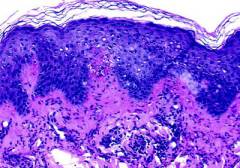

Уртикарный васкулит

Уртикарный васкулит можно рассматривать как разновидность аллергического васкулита. Синоним названия заболевания — Заболевание встречается редко. Внешне напоминает аллергическую реакцию по типу крапивницы.

Симптомы уртикарного васкулита:

Основной симптом уртикарного васкулита – сыпь. Она напоминает таковую при крапивнице: на коже появляются волдыри красного цвета.

Различия между сыпью при крапивнице и уртикарном васкулите:

| Характеристика | Крапивница | Уртикарный васкулит |

| Плотность волдырей | Средняя | Очень плотные |

| Как долго держится сыпь? | Кратковременная, быстро проходит после прекращения контакта с аллергеном. | Держится дольше 24 часов, обычно 3 – 4 суток. |

| Есть ли зуд? | Есть. | Нет, вместо него отмечается боль, жжение. |

| Что остается на месте сыпи после ее исчезновения? | Проходит бесследно. | Остаются подкожные кровоизлияния, синяки зеленого и желтого цвета, пигментные пятна. |

| Нарушается ли при этом общее состояние пациента? | Практически не нарушается. Основные проблемы связаны с зудом. | Нарушается, отмечается повышение температуры тела. |

| Поражаются ли другие органы? | Характерные симптомы аллергических реакций: